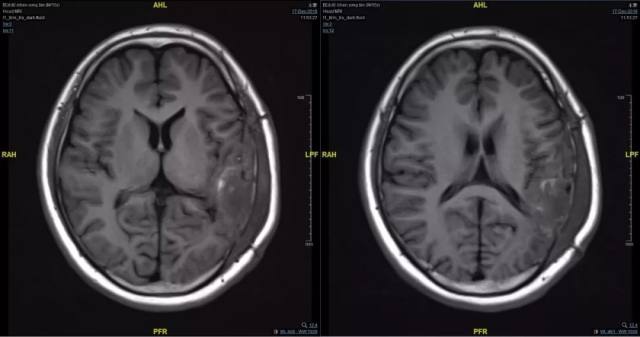

5、术后影像